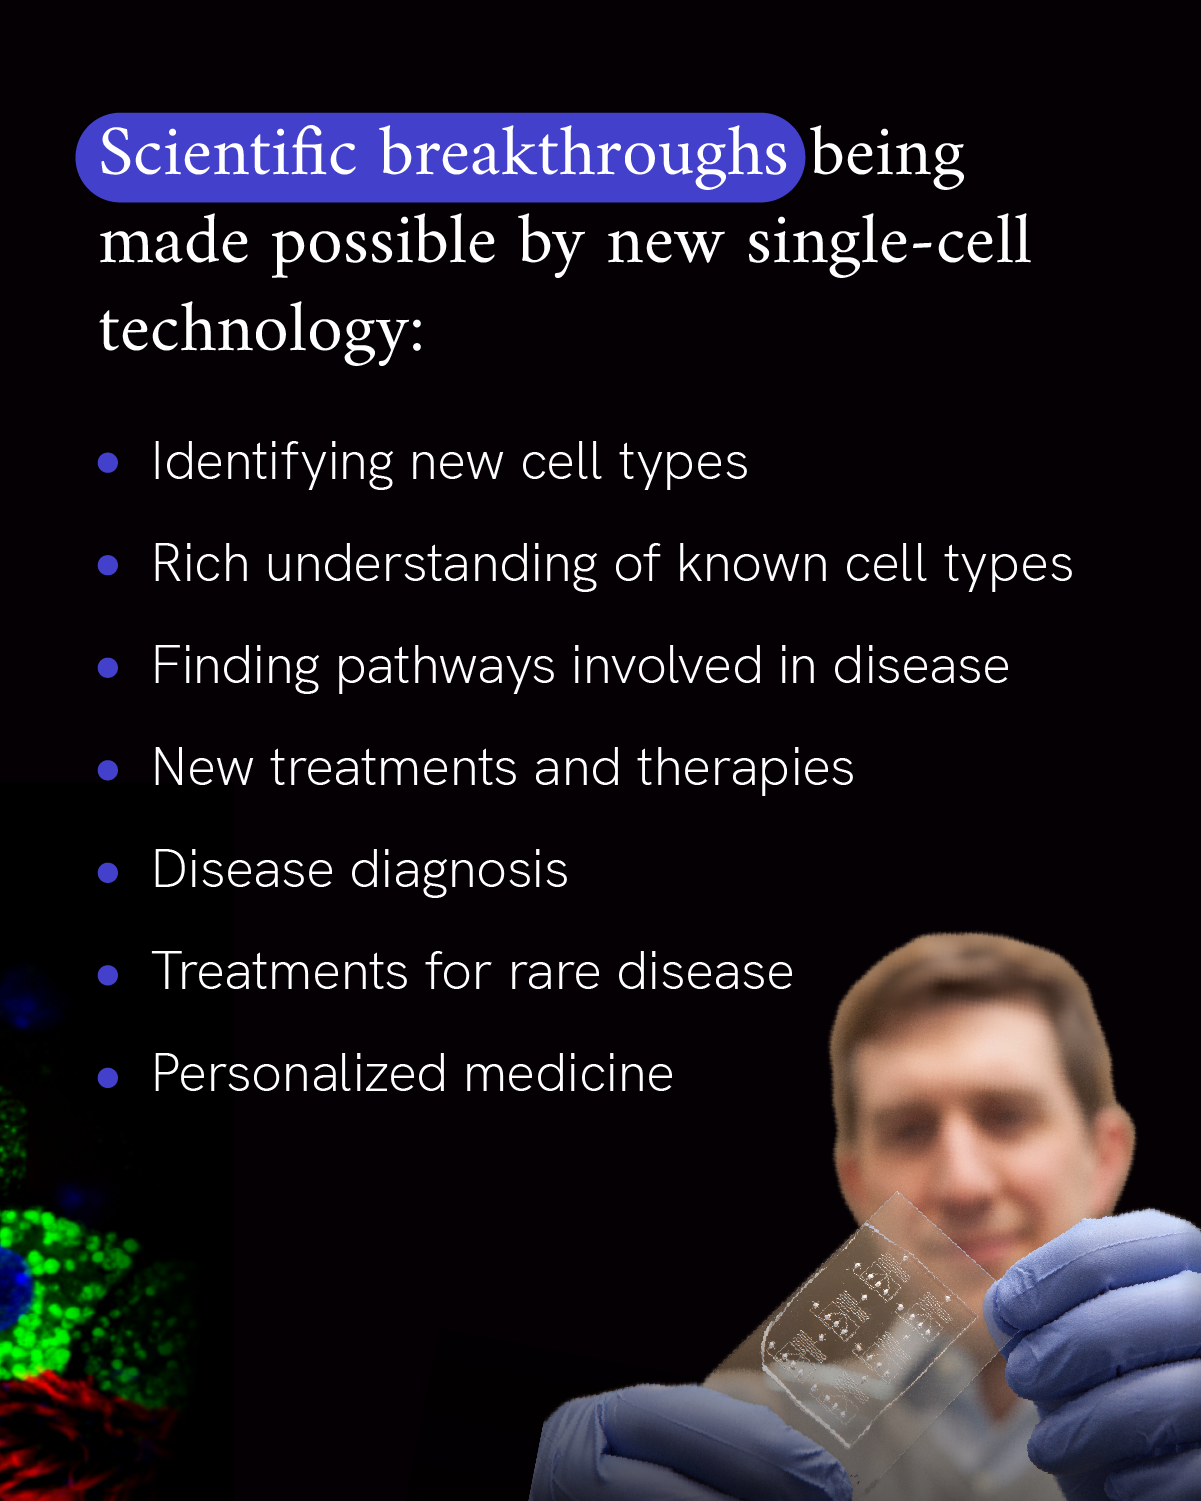

Historically the answer has been that there are about 200 different types of cells in the human body, but new technology in the last decade has uncovered many more than that, totalling a couple thousand.

But it’s taken advances of imaging technology and molecular biology to fully begin to realize just how varied cells can be. For example, the Tabula Sapiens is a project by the Chan Zuckerberg Biohub San Francisco and CZI to map cells of the human body using molecular data. They have already characterized over 400 different cell types using molecular data from studying 500,000 cells from 24 different tissues and organs. The data in these comprehensive cell atlases put a spotlight on the subtle differences between cells that are key to maintaining health, and help us better detect the early changes that lead to disease.

In neurodegenerative diseases like Parkinson’s and ALS, these non-regenerating cells are lost, leading to symptoms of disease. By bringing together researchers from unique disciplines, we want to enable earlier and more accurate diagnosis of neurodegenerative disease and find new treatments.

Diseases result from a change in our body’s function, right down to the level of our cells. By studying which cells are affected in a disease and what changes are happening to everyday cell processes, researchers will be better poised to treat the root cause of a disease. That’s because understanding more about the biology of a disease can enable researchers to identify new targets for medications, better understand disease progression, make more personalized predictions of how someone may respond to a treatment, and develop preventative measures for disease.

For example, rare diseases often involve specific genetic mutations or changes to how genes and proteins are regulated, which point to the role they play in our cells. Through the CZI Patient-Partnered Collaborations for Rare Neurodegenerative Disease and Single-Cell Analysis of Rare Inflammatory Pediatric Disease, researchers and patient organizations are partnering to accelerate our understanding of some of the more than 7,000 rare diseases affecting more than 300 million people worldwide. This work not only advances us towards new treatments for these diseases, but gives us a better understanding of basic cellular processes that are important to treating common diseases, too.